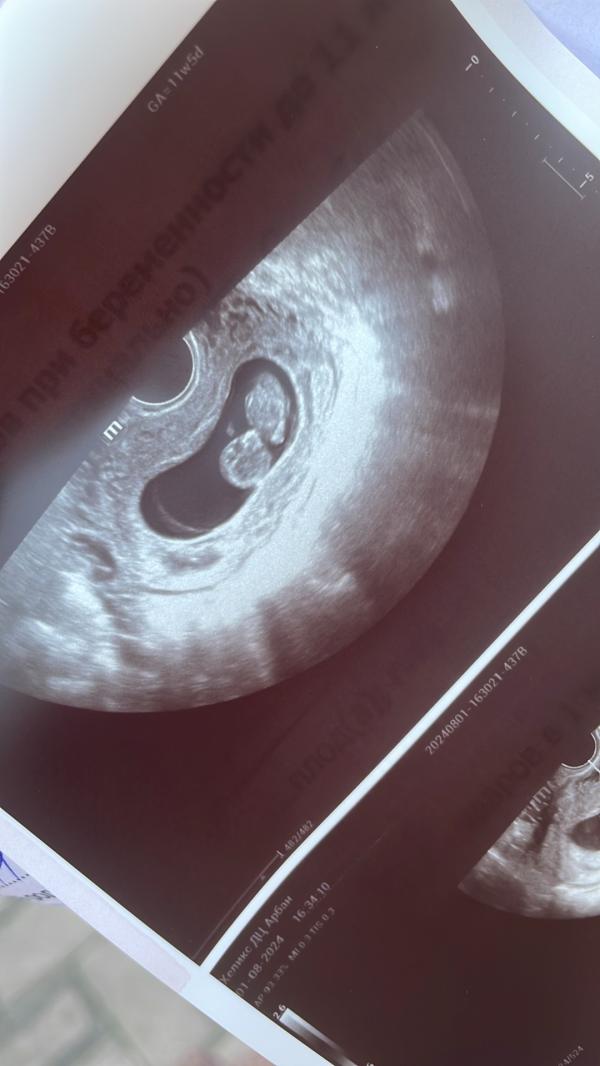

УЗИ: радость и тревога

post image

Я и моя тревожность 😅 просто записалась на узи платно за неделю до скрининга ,потому что не могу терпеть ,что бы узнать ,что все в порядке 🙃 Мне кажется врач узи подумала ,что я ку ку ) но зато увидела малыша ,у него дискотека была в животе ,до сих пор не верится ,что это мое ,что я буду дважды мама ) по месячным и по узи разница всего 2 дня )

Там что два?? 😀

это голова и туловище кажется

Один😂 мама и свекровь тоже так подумали ,просто он сильно активный был и только такое фото получилось ,на видео конечно интереснее смотреть )